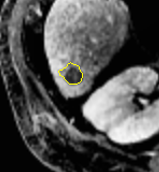

2.

Edge-Aware 3D Image Segmentation Networks

[91]: Automated segmentation of kidneys and kidney tumors is an important step in quantifying the tumor’s morphometrical details to monitor the progression of the disease and accurately compare decisions regarding the kidney tumor treatment. Manual delineation techniques are often tedious, error-prone and require expert knowledge for creating unambiguous representation of kidneys and kidney tumors segmentation. We propose a 3D end-to-end edge-aware FCN for reliable kidney and kidney tumor semantic segmentation from arterial phase abdominal 3D CT scans. Our segmentation network consists of an encoder-decoder architecture that specifically accounts for organ and tumor semantics. We evaluate our model on the 2019 MICCAI KiTS Kidney Tumor Segmentation Challenge dataset. -